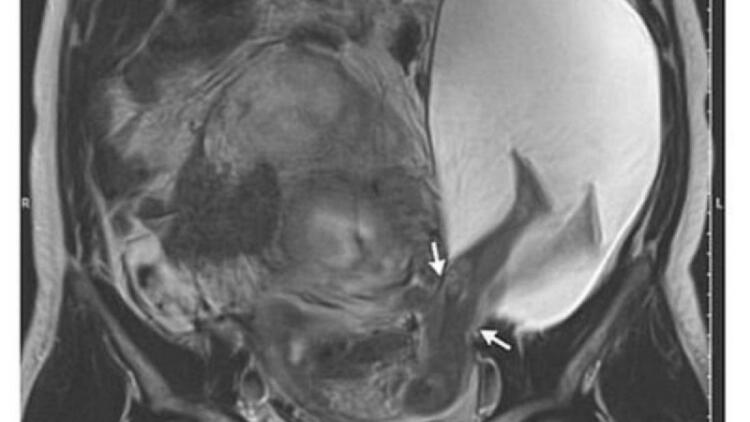

Συγκεκριμένα, μια έγκυος γυναίκα στην Κίνα σώθηκε χάρη στους γιατρούς, αφού το αγέννητο μωρό της κλώτσησε τη μήτρα της σε μια “εξαιρετικά σπάνια” περίπτωση. Η αγέννητη κόρη της κ. Ζανγκ λέγεται ότι κλώτσησε την ίδια τόσο σκληρά, που έσκαψε μια πληγή στον τοίχο της μήτρας της, η οποία είχε μείνει από μια προηγούμενη εγχείρηση.

Το κοριτσάκι γεννήθηκε στις 35 εβδομάδες με καισαρική τομή και η ίδια αλλά και η μητέρα της βρίσκονται σε σταθερή κατάσταση, σύμφωνα με το Νοσοκομείο Shenzhen του Πανεπιστημίου του Πεκίνου στη νότια Κίνα.